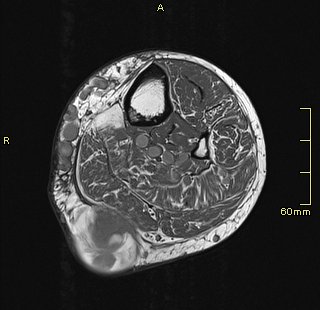

La radióloga con estos datos decide ampliar el estudio con RMN donde se observa que la lesión tiene aspecto heterogéneo con áreas hipo intensas sobre todo centrales con artefacto ferromagnético con secuencias en eco gradiente que puede sugerir la existencia de restos de hemosiderina y áreas hiperintensas sugerentes de necrosis como ves en la imagen 9.

La lesión impronta de forma importante al gemelo medial y parece infiltrar a la fascia del mismo.

Desde el punto de vista técnico y sin entrar en más detalles ya que este blog es de eco y el que escribe no da para más, te enseño cuatro cortes de RMN de la lesión estudiada posteriormente a la ecografía.

La imagen 6 te muestra un corte anatómico potenciado en T1 que nos va a mostrar relación anatómica de las estructuras. Cuando veas la imagen 7 y 8 te irás dando cuenta que la patología se muestra mucho más marcada ya que son corte axial y sagital y potenciado en un T2.

Puedes ver el comportamiento de la lesión en ambas potenciaciones y en al menos dos cortes ortogonales.